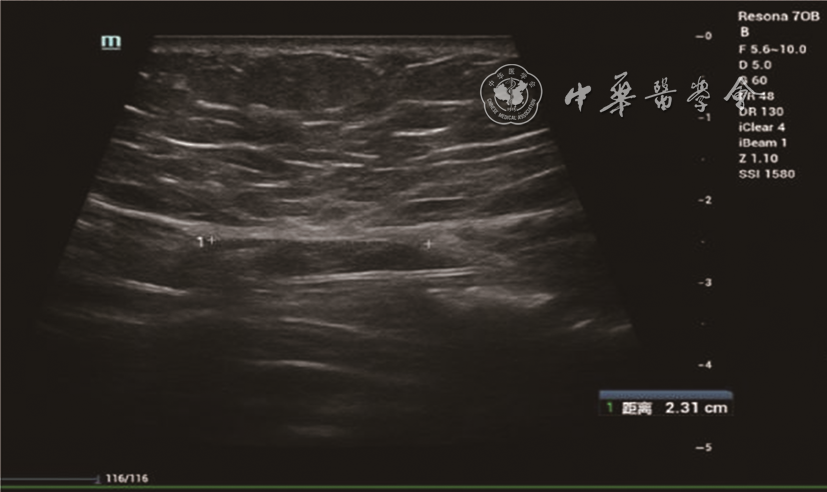

2. 方法:受检者平躺,暴露腹部检查区域,采用横向、纵向、斜向多平面结合方式先进行实时二维灰阶扫查,观察剑突以下至耻骨联合以上的腹直肌情况,测量脐水平、脐上5 cm水平、脐下5 cm水平的双侧腹直肌高回声筋膜内侧缘间的距离,记录为IRD0、IRD+5、IRD-5图12)。二维超声定位双侧腹直肌内侧1~2 cm范围内的部位,嘱患者屏气3~5 s,开启SWE扫查模式,剪切波弹性的量程为0~180 kPa,待图像稳定后冻结,选择感兴趣区域(region of interest,ROI),ROI范围为双侧腹直肌内侧1~2 cm的最大测量面积(不包括腹直肌筋膜),手持探头在检测部位,不施加压力。双幅实时显示功能观察二维图与弹性图,选取ROI,静置3~5 s,保持探头稳定以获得稳定弹性图(M-STB Index:5颗绿星)并保存,观察和记录该区域弹性模量颜色分布特征。仪器自带Q-BOXTM定量测量工具,测量ROI范围内杨氏弹性模量值[平均值(Emean)、最大值(Emax)、最小值(Emin)],每个区域(右侧腹直肌脐水平R0、左侧腹直肌脐水平L0、右侧腹直肌脐上5 cm水平R+5、左侧腹直肌脐上5 cm水平L+5、右侧腹直肌脐下5 cm水平R-5、左侧腹直肌脐下5 cm水平L-5)中部水平测量2次,取平均值(图34)。

图2 35岁初产妇产后43 d,脐上5 cm水平双侧腹直肌间距为2.3 cm